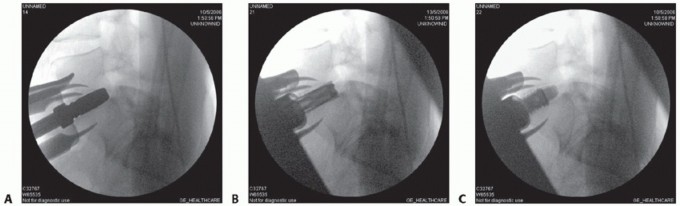

- TECH FIG 4 • AP (A) and lateral (B) fluoroscopic images showing midline positioning and screw trajectories of stand-alone ALIF device.

Typically, a single interbody cage that spans the disc space is selected, with graft material packed on both sides within the implant. This is positioned in the center of the interspace using product-specific instruments (TECH FIG 4A).

Locking screws are directed cephalad and caudad either through the cage device or through a metal faceplate that attaches to the cage (TECH FIG 4B). Knowledge of productspecific screw trajectories and starting points is paramount as they may be either symmetric about the midline or translated left or right to allow safe passage of the drill between the iliac vessels. - Adjunct Treatments

Under fluoroscopic guidance, determine the midline on a true AP image of the vertebral body above or

below the disc (TECH FIG 5A). A bone screw may be inserted as a reference.

Sizing guides are trialed to fill the entire footprint of the endplate (TECH FIG 5B). Height and lordosis are then set using trial wedges (TECH FIG 5C-E) and should match the resected gap and preoperative templating.

- TECH FIG 5 • A. True AP fluoroscopic image. The distance between the midpoint of the vertebra and the pedicles should be the same. The cortical margins of the pedicles themselves should be the same size (ensuring the spine is not rotated). Finally, the spinous processes should bisect the vertebra. The spinous processes are the least reliable landmark as they can be malformed, especially at L5 and S1. B. A sizing guide, or “lollipop,” demonstrates how well the endplate will be covered by the final implant. The largest size that allows good peripheral endplate coverage in both the sagittal and coronal planes is desired. C-E. Using radiolucent trial wedges of varying height and lordosis allows the final device to be individualized to the patient's anatomy. F. Introduction of the channel cutter into the disc space. G. Lateral fluoroscopic image showing implant insertion. The insertion instruments are still connected, which allows for fine adjustment to the final positioning. H,I. Lateral and AP fluoroscopic images of the final TDR placement with all of the instruments removed. The final implant should be in the center of the vertebral

body on the AP image and in the center (sagittal midline) or just posterior to the center of the vertebral body on the lateral image. (B-E: Courtesy of DePuy Spine, Raynham, MA.)

An implant-specific chisel is then directed straight posteriorly through the bodies to cut a groove for the keel or teeth that align the implant and prevent rotation (TECH FIG 5F) and the final implant inserted (TECH FIG 5G-I).